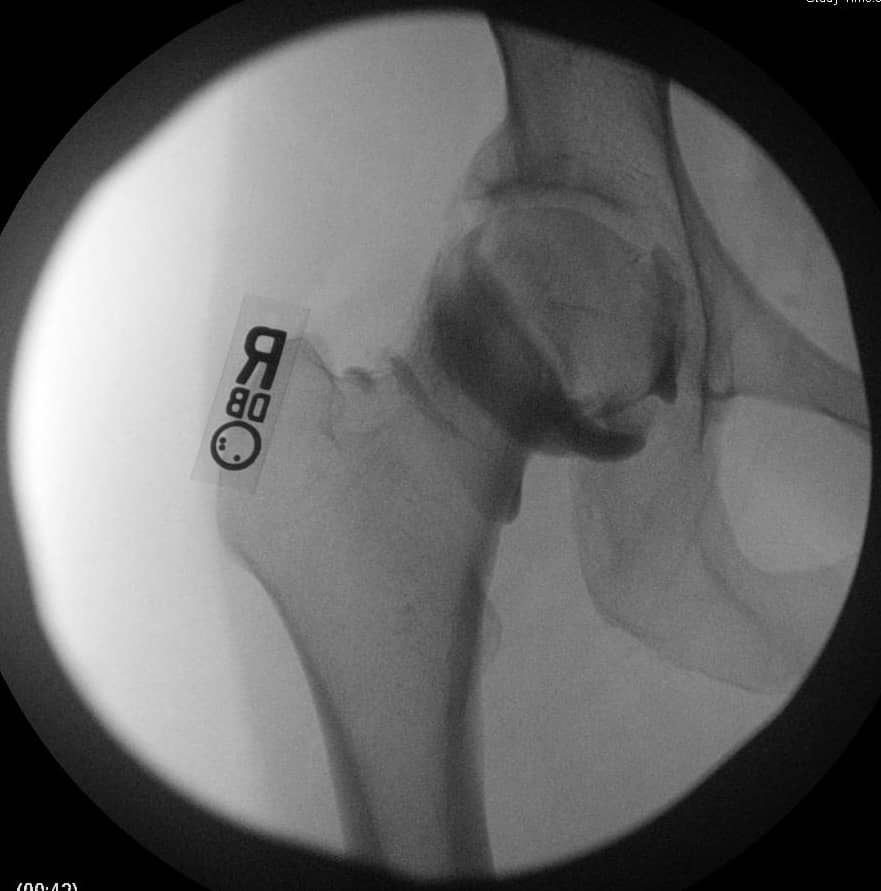

एक एपी श्रोणि दृश्य प्रभावित और अप्रभावित फेमोरा की तुलना की अनुमति देता है। यह सुनिश्चित करने के लिए समरूपता का आकलन करें कि एक सच्चा एपी दृश्य कैप्चर किया गया है। इसका आकलन यह जांचकर किया जा सकता है कि कोक्सीक्स सिम्फिसिस पबिस को ओवरलैप करता है, जिसमें दो संरचनाओं के बीच 2 सेमी से अधिक अलगाव नहीं होता है। संयुक्त स्थान में कमी और अपक्षयी परिवर्तनों के लिए संयुक्त का मूल्यांकन किया जाना चाहिए। अप्रभावित पक्ष के साथ एंटेरोलेटरल गर्दन समोच्च की तुलना करें। बेहतर गर्दन की शंकु की कमी सिर-गर्दन ऑफसेट को कम करने का संकेत देती है। एंटेरोसुपीरियर या पूर्ववर्ती सिर की सपाट या बढ़ी हुई त्रिज्या एक गोलाकार सिर को इंगित करती है। कई मापों का विश्लेषण किया जा सकता है:

- एफएआई के मूल्यांकन के लिए एक क्रॉस-टेबल पार्श्व दृश्य महत्वपूर्ण है, जिससे एंटेरोलेटरल फेमोरल गर्दन का दृश्य देखने की अनुमति मिलती है।

- अल्फा-कोण: ऊरु गर्दन की मध्य रेखा के साथ एक रेखा और ऊरु सिर के केंद्र से उस बिंदु तक एक रेखा के बीच बनता है जहां अतिरिक्त हड्डी सामान्य ऊरु सिर स्फेरिसिटी से विचलित होती है। 60 डिग्री से अधिक का कोण एफएआई को इंगित करता है।

- सिर-गर्दन ऑफसेट: ऊरु गर्दन के अनुदैर्ध्य अक्ष को विभाजित करने वाली रेखा से शुरू करें। एक समानांतर रेखा खींचें जो ऊरु गर्दन के पूर्ववर्ती पहलू के लिए स्पर्शरेखीय है और पूर्ववर्ती ऊरु सिर के समानांतर रेखा स्पर्शरेखा की दूरी को मापें। सामान्य दूरी 9 मिमी से अधिक है या सिर के व्यास का अनुपात 0.17 से अधिक है।